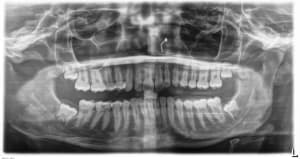

10-07-2025 Panoramique Fin.JPG